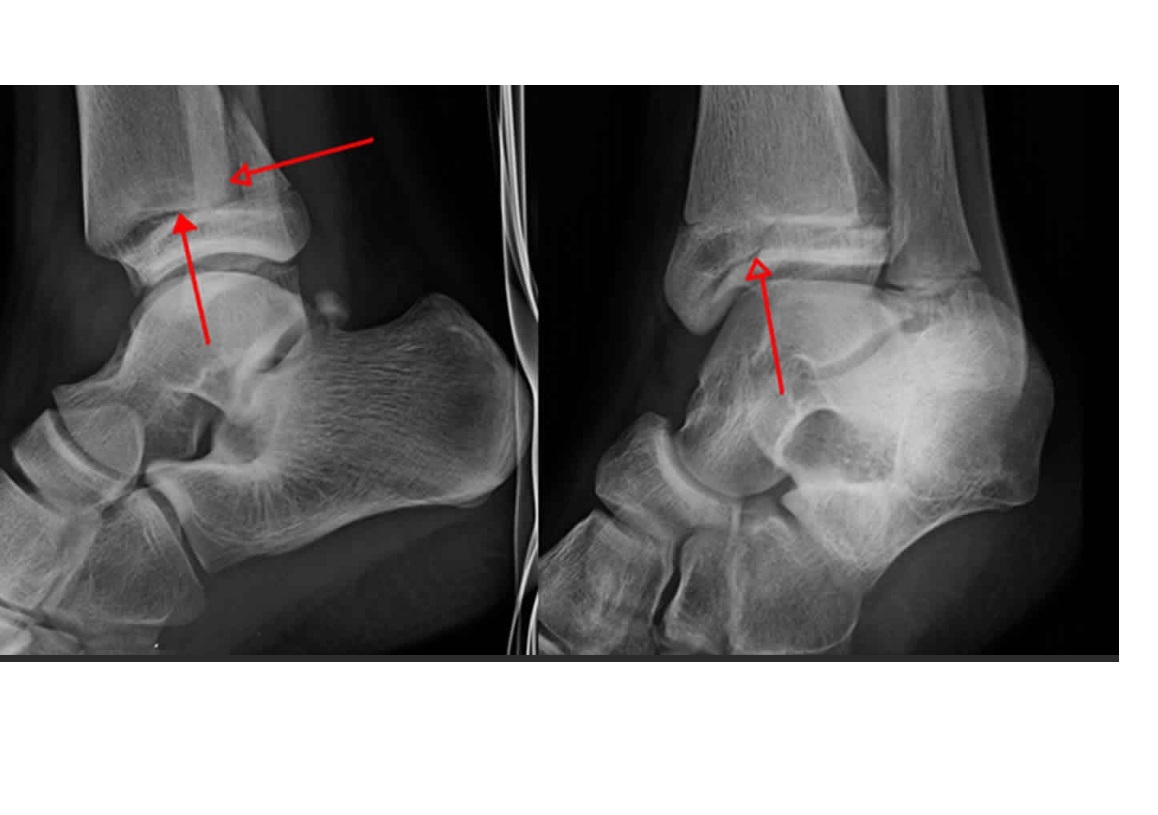

Calcaneonavicular vs talocalcaneal coalitions

see picture